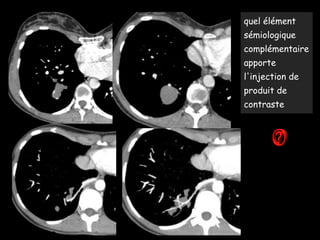

quel élément

sémiologique

complémentaire

apporte

l'injection de

produit de

contraste

.Masse bien

limitée, contours

nets

.Pas de connexion

avec l’arbre

bronchique

.thorax creux